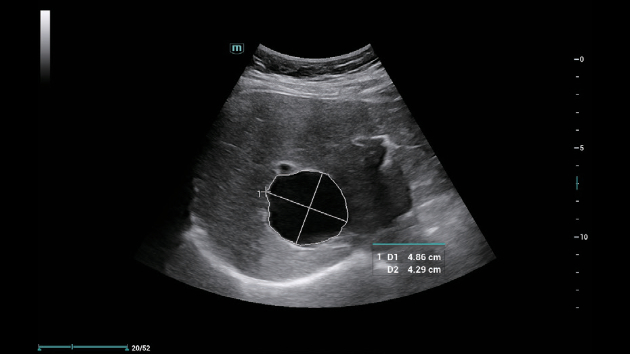

A linha Consona apresenta solu??es inovadoras e eficientes que o ajudam a realizar diagnÃģsticos em diversos tipos de pacientes.

N?o importa se sua rotina ÃĐ em hospitais, clÃnicas ou se vocÊ estÃĄ aprimorando habilidades em Imagem Geral, SaÚde da Mulher ou na ÃĄrea Cardiovascular; vocÊ encontrarÃĄ ferramentas altamente poderosas disponÃveis para manter-se na vanguarda.

Solu??es abrangentes de imagens com tecnologia ZST+

A plataforma ZST+ ÃĐ uma inova??o extraordinÃĄria, representando a evolu??o do ultrassom. Transformando as mÃĐtricas de ultrassom: da forma??o convencional do feixe ao processamento baseado em dados de canais. Supera a limita??o de compensa??o tradicional entre resolu??o espacial, resolu??o temporal e uniformidade de tecido, oferecendo qualidade de imagem excepcional para solu??es de imagem infinitas com melhorias inigualÃĄveis.